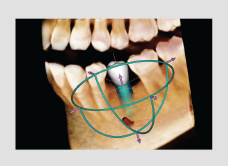

• 3 click implant simulation

• Collision detection

• Bone density

• Oblique view mode

• Adjustable automatic implant collision detection function between multiple implants and/or nerve canal